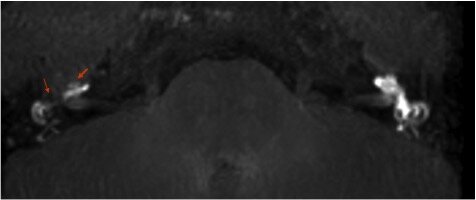

Visualizzazione dell’idrope endolinfatico mediante Risonanza Magnetica

La tecnica prevede la somministrazione per via intra-timpanica del comune mezzo di contrasto paramagnetico (gadolinio) diluito in soluzione fisiologica. A distanza di 24h dalla somministrazione, si effettua una RM con tecnica FLAIR utilizzando una apparecchiatura ad elevata potenza (3Tesla). Il liquido di contrasto si diffonde progressivamente negli spazi perilinfatici delineando, in assenza di idrope, tutta l’anatomia labirintica. Nei pazienti menierici, per contro, si osserva una ridotta visualizzazione del mezzo di contrasto, a causa alla distensione idropica del labirinto membranoso che occupa spazio a spese della perilinfa. Nella figura sottostante si osserva sulla destra l’immagine dell’intero labirinto. L’orecchio controlaterale, il sinistro, evidenzia invece una ridotta visualizzazione della coclea e del vestibolo a causa dell’idrope.

La possibilità di visualizzare l'idrope endolinfatico apre delle interessanti prospettive in ambito diagnostico e terapeutico. In particolare consente di effettuare unadiagnosi di certezza della presenza di idrope ed orientare il trattamento terapeutico.